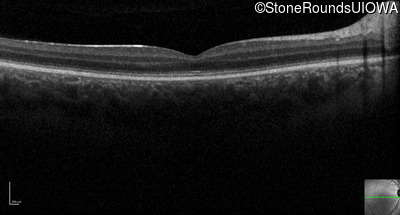

Optical Coherence Tomography - Right - 10/100

Exemplar / OCT Stack

Optical Coherence Tomography - Left - 10/100